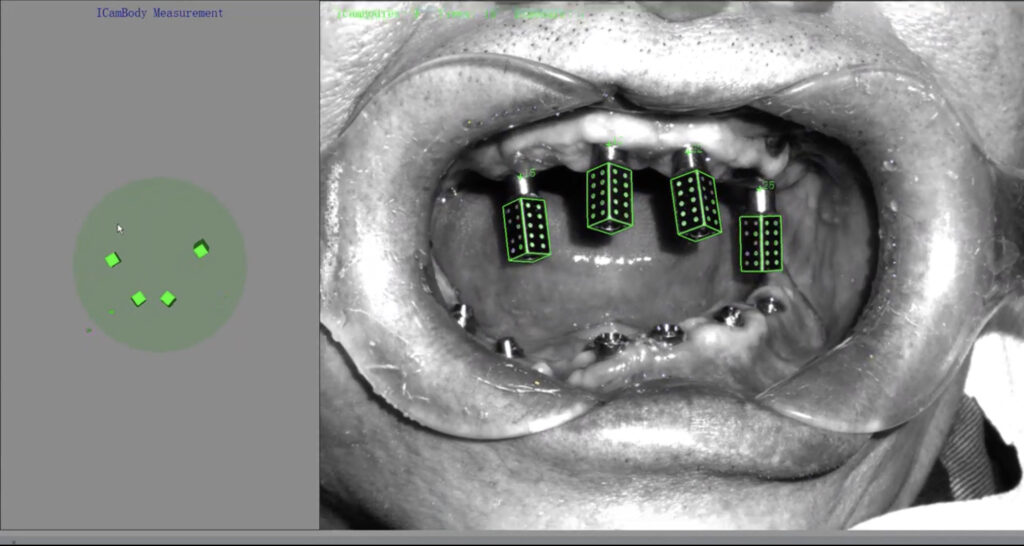

Fig.3: Extraoral photogrammetry, Icam4D [Imetric, Switzerland (3rd generation)]; (a) Icam4D radiopaque titanium SBs.

(b) EPG camera system combines structured light and photogrammetric scans to capture three-dimensional data

(c) The exact position of EPG scan bodies is automatically identified by the software